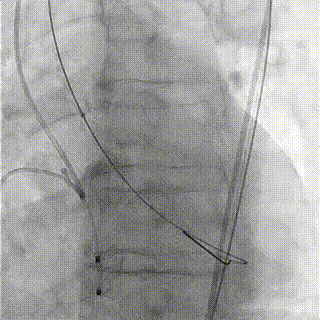

患者为功能型二叶瓣,瓣叶增厚,重度钙化,右无可见钙化融合,左无局部粘连,瓣环平面仍可见钙化,双冠脉高度尚可,瓣叶未见冗长,考虑冠脉风险较低,心脏角度约51°,考虑瓣环平均直径26.4mm,流出道平均直径24.8mm,短径为23mm,选择23球囊预扩,结合中国人群二叶瓣比例高,钙化重,故选择径向支撑力强的启明第三代可回收Venus-A Pro 29mm瓣膜。

球囊预扩

球囊后扩